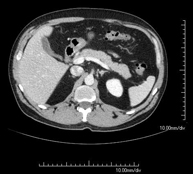

- TC Abdomen

Prova diagnòstica que consisteix en l'estudi de l'abdomen d'alta definició anatòmica (fetge, vesícula biliar, via biliar, pàncrees, melsa, estómac, intestins, ronyons, estructures vasculars, bufeta, úter i ovaris, etc.) mitjançant l'ús d'un equip de TC (Tomografia Computeritzada). Aquestes imatges s'estudien posteriorment en una estació de treball que permet obtenir reconstruccions bidimensionals en diferents plànols de l'espai i també reconstruccions 3D (volumètriques). La majoria d'estudis requereixen l'ús de contrast iodat per millorar la definició de les imatges. - TC Pelvis

Prova diagnòstica que consisteix en obtenir imatges bi i tridimensionals de l'abdomen d'alta definició anatòmica (estructures òssies, estructures vasculars, fetge, pàncrees, vesícula biliar, ronyons, glàndules suprarenals, melsa, intestí prim i gros, bufeta, úter i ovaris, pròstata i vesícules seminals, urèters, etc.) mitjançant l'ús d'un equip de TC (Tomografia Computeritzada). La majoria d'estudis requereixen l'ús de contrast iodat. - TC Fetge